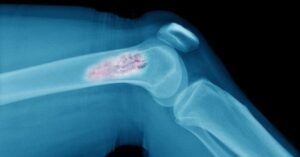

Vücuttaki kemik dokusunda anormal ve hücresel olarak kontrolsüz büyümeyle karakterize edilen bir tümör türüdür. Genellikle kemik ağrısı, şişlik ve kırıklar gibi semptomlara neden olabilir. Kemik tümörü, iyi huylu veya kötü huylu olabilir ve çeşitli faktörlere bağlı olarak gelişebilir. Tanı ve tedavi genellikle radyolojik görüntüleme, biyopsi ve cerrahi müdahale gerektirir.

Kemik Tümörü Belirtileri Genellikle ağrıya neden olur. Bu ağrı sürekli veya dinlenme halinde artan bir karaktere sahip olabilir. Ağrı, tümörün büyümesiyle birlikte artabilir. Kemik üzerinde veya yakınında anormal bir şişlik veya şişkinlik hissedilebilir. Bu, büyümesiyle ortaya çıkabilir. Kemiklerin zayıflamasına neden olabilir, bu da kırık riskini artırır. Özellikle kemiklerde ani bir kırık oluşumu veya tekrarlayan kırıklar, kemik tümörü belirtisi olabilir. Eklemleri veya kasları etkileyebilir, bu da hareket kısıtlılığına neden olabilir.